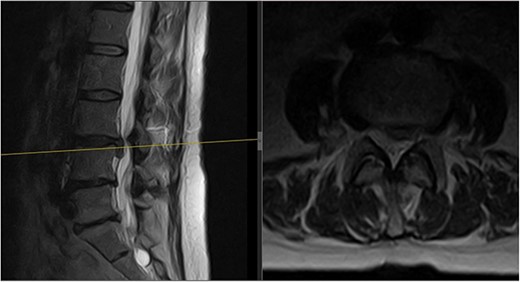

Three months later, the patient noted significant pain reduction. A physical exam revealed an increased range of motion with the patient able to reach her toes whilst flexing forward. No neurological deficits were present. Repeat MRIs showed improvement and resorption of the disc material at L3/L4, relieving the compression on the L4 nerve root (Fig. 3).

Follow-up MRI scan of the lumbar spine: follow-up MRI scan of the lumbar spine performed in March 2023 showing complete resolution of the disc prolapse.